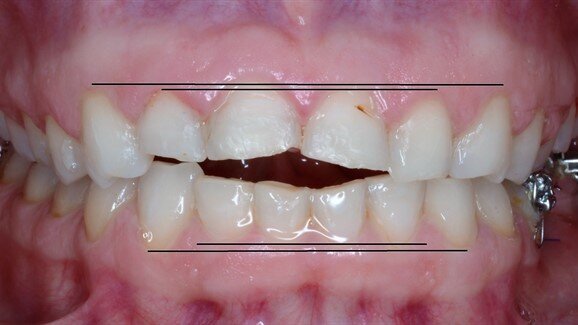

Studiile, efectuate în colaborare de către Departamentul de Biologie Celulară, Fiziologie și Imunologie al Universității din Barcelona și Departamentul de Știință a Sportului al Universității din Innsbruck, au găsit o relație între malocluzie și controlul postural. Ambele studii furnizează date concludente care arată că are loc îmbunătățitrea controlului postural-atât în echilibru static, cât și dinamic-atunci când sunt corectate diferite malocluzii prin poziționarea maxilarului într-o poziție neutră.

Primul studiu a luat în considerare tipul de ocluzie dentară și existența unui tratament ortodontic anterior. Rezultatele au arătat faptul că modificarile de aliniere a dinților au fost legate de un control deficitar al echilibrului static.

Al doilea studiu a evaluat tipul de ocluzie dentară, controlul posturii și oboseala fizică, în scopul analizării existenței unei posibile relațiii între acești factori. Acesta a demonstrat faptul că echilibrul s-a îmbunătățit atunci când au fost corectate malocluziile și că, acestea din urmă, au avut un impact mai mare asupra controlului postural atunci când subiecții erau obosiți decât ăn cazul în care ei erau odihniți.

"Atunci când există o malocluzie, acesta este clasificată conform criteriilor stabilite în mod științific. Ceea ce este relevant în studiu este faptul că malocluziile au fost asociate și cu alte modificări motorii și fiziologice", a explicat Julià-Sánchez. Această relație nu este evidentă în condiții statice de zi cu zi, cu toate că pot exista stări asociate cu patologii cum ar fi obezitatea, care agravează instabilitatea corpului, reducând astfel controlul postural și crescând riscul de cădere.